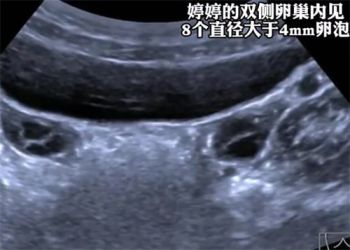

7岁女童3个月猛蹿4cm确诊性早熟

详

发育了就直接描述特征,干嘛强调身高,3个月长4厘米不要太正常。

长快也不行长慢也不行。

控制饮食,没那么严重,我家孩子也是7岁确诊,现在快十一岁,一米六多,还没来大姨妈。